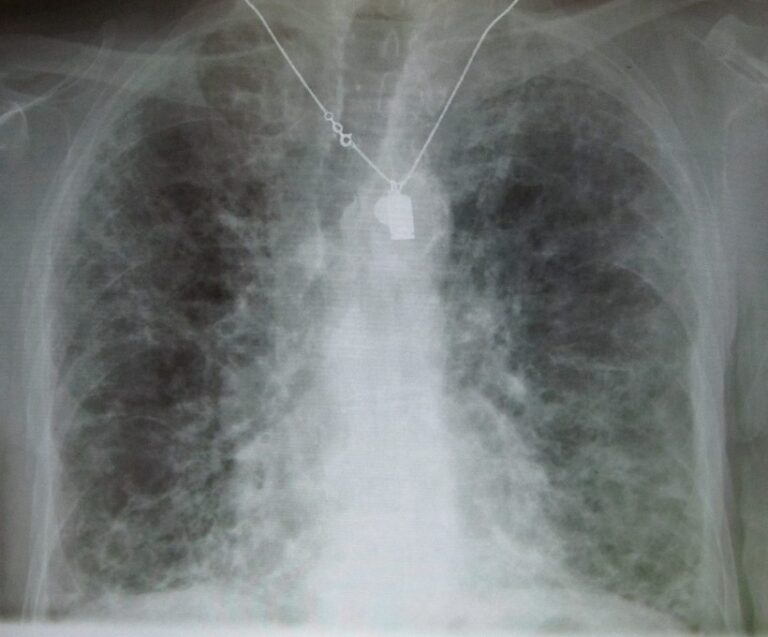

Když se člověk řízne, rána se obvykle zacelí a na místě zůstane jizva. Na kůži jde o více či méně estetický problém, pokud se však jizvy objeví na plicích, mohou zabíjet. Zjizvená, tj. fibrotická tkáň totiž neumožňuje průchod kyslíku.

Plicní fibróza (PF) je závažné onemocnění, při němž dochází ke zjizvení původně zdravé plicní tkáně a k jejímu ztluštění a ztuhnutí. Pacient tak ztrácí plochu k dýchání a postupně se u něj snižuje schopnost nadechnout se.

Mezi nejčastější projevy PF patří zvýšená dušnost, a to už při vykonávání mírné fyzické aktivity, chronický kašel, paličkovité prsty (rozšířené a zakulacené konečků prstů na rukou nebo nohou), únava a postupné neúmyslné ubývání na váze.